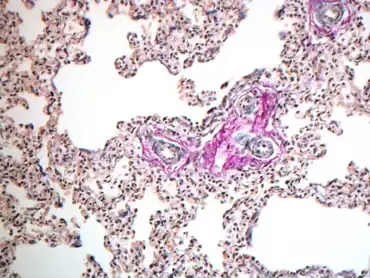

- Decreased diameter of pulmonary vessels with hypertrophy of vessel walls: This has a poor prognosis, as it is a fixed abnormality. Causes include post-term pregnancy, placental insufficiency, and NSAID use by the mother.